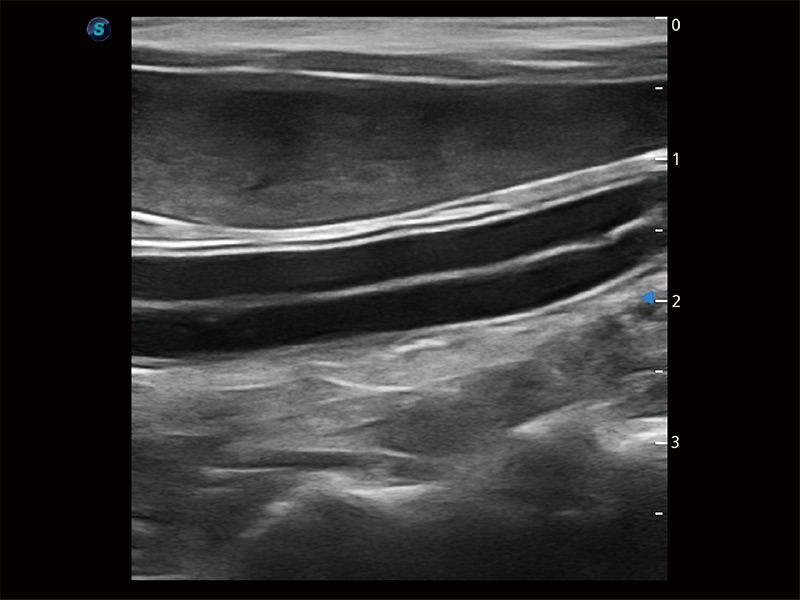

極大提升超低速微細(xì)血流的檢出能力,同時更精準(zhǔn)地濾除軟組織和超聲信號,為獸用醫(yī)生提供以往無法通過常規(guī)血流獲得的疾病診斷信息。

在傳統(tǒng)二維血流成像的基礎(chǔ)上,呈現(xiàn)血流的立體感,具有動感的生命力之美。即便是微小的血管也能輕松應(yīng)對,提高了血流的視覺敏感性。